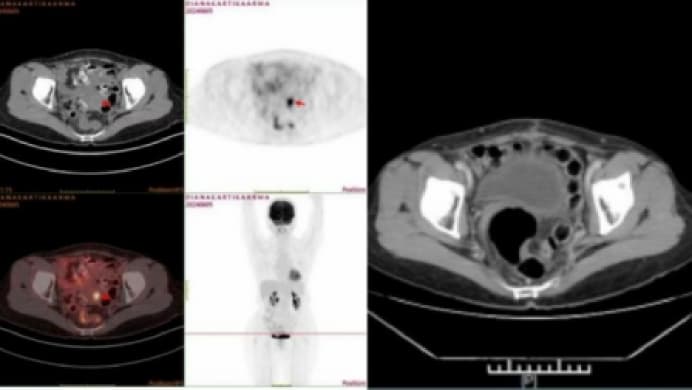

Diana Kartika Arma,

Diana Kartika Arma, kanker serviks stadium IB2B - telah bertahan 3 tahun.

Tim MDT RS kemudian merancang sebuah rencana pengobatan untuknya, termasuk terapi bertarget, terapi natural, dan imunoterapi.